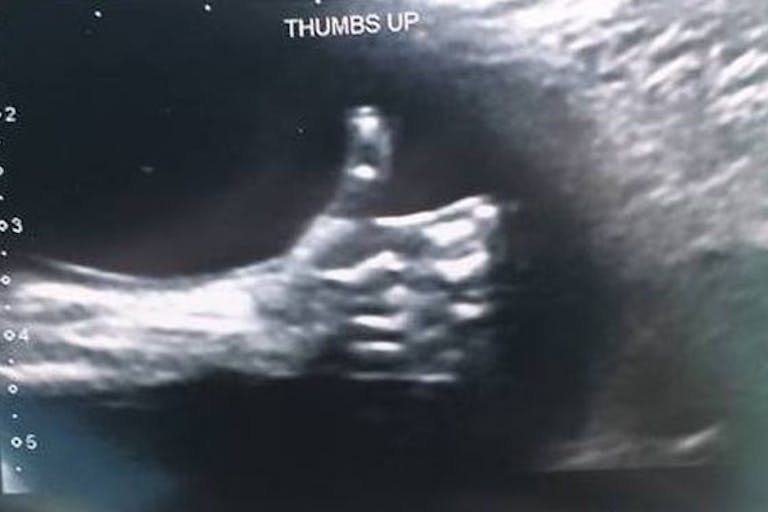

‘Incredible’ ultrasound photo shows baby boy giving parents a thumbs up

Nicole Kim was feeling a bit down before she went in for the 20 week ultrasound of her third baby. Her husband Tony had recently been laid off from his job, but on this day, Kim was more focused on learning if she would be having a baby girl or boy. Still, when her preborn son gave her an adorable thumbs up, Kim felt reassured about her family’s future.

Kim told the Calgary Herald that the technician saw the thumbs up and quickly zoomed in to snap the uplifting photo, which is now displayed in a frame at the family’s home. After sharing the ultrasound image on Facebook, it went viral.

“For me, it just made it seem like everything was going to be OK,” Kim told TODAY. “Living in Calgary, there’s a lot of people being laid off right now, and it’s hard for our families. We know two other families dealing with it. I think the reason this went viral was because people wanted something to be happy about.”

Baby boy Kim is due this summer and his big brothers, ages 3 and 5, are eager for his arrival, kissing and hugging their mom’s belly. They think the thumbs up their baby brother gave is pretty cool.